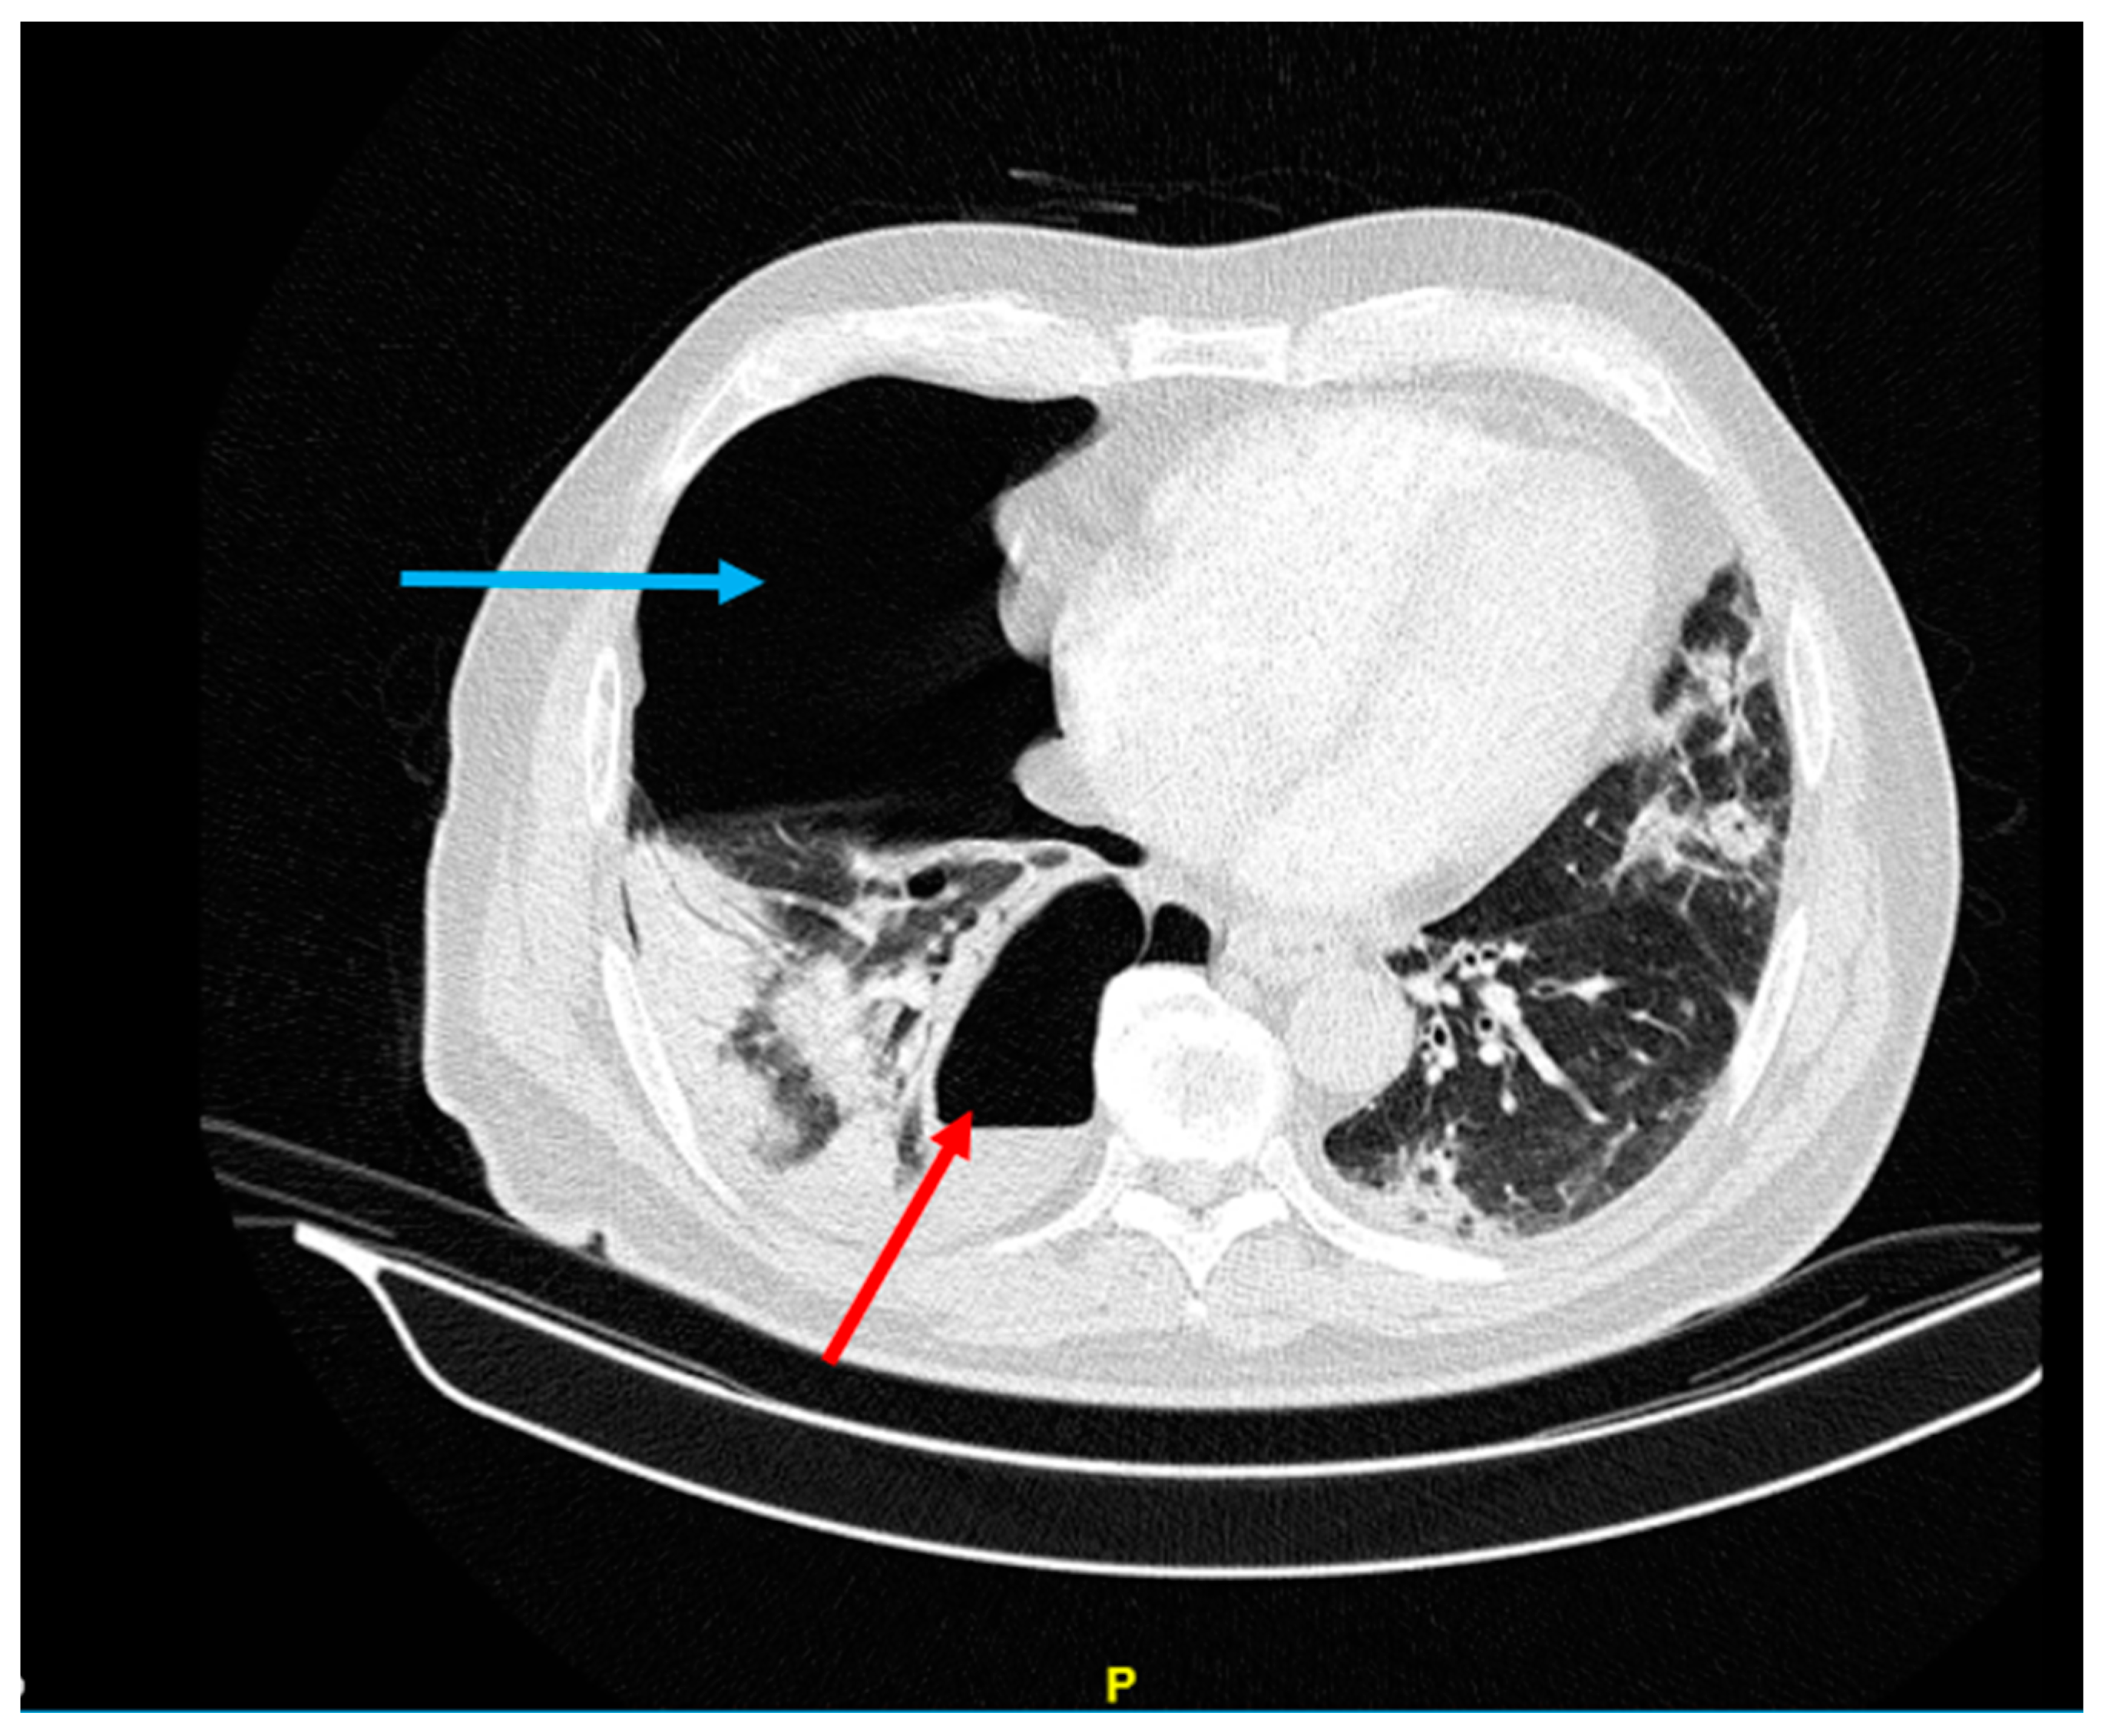

However, three weeks later, the patient developed shortness of breath symptoms with a dry cough and bilateral chest pain and was referred to the respiratory unit of the Valiasr Hospital in Zanjan, Iran. On admission, her SpO2 was 76%, her BP was 100/70 mmHg, her PR was 84/min, her RR was 21/min, and her T was 37.8 °C. Although her throat and nasal samples were negative for COVID-19, a non-contrast lung CT revealed typical COVID lung involvement with the presence of large septoid cavities in both the right and left lungs. In particular, a large cavity with an air-fluid level was observed in the left lower lobe, while a similar cavity was seen in the right upper lobe which extended to the middle and lower lobes (Figure 1 and Figure 2).

Figure 1.

Large septoid cavity in right upper lobe with the spread to the middle and lower lobes of the lung (red arrow).

Figure 2.

Large cavity with the air-fluid level in the left lower lobe (red arrow).